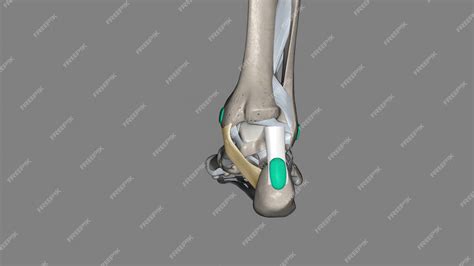

The flexor retinaculum is a thick, fibrous band that stretches from the medial malleolus—the bony prominence on the inside of your ankle—to the medial tubercle of the calcaneus, or heel bone. Its primary purpose is to act as a ligamentous sheath, binding down the tendons of the deep muscles of the posterior compartment of the leg.

By holding these tendons close to the ankle bone, the flexor retinaculum foot structure prevents "bowstringing" during movement. When the muscles in your calf contract to point your toes downward or flex your foot, these tendons would naturally pull away from the bone if not for the restraining force of the retinaculum. This allows for efficient transfer of force, enabling smooth walking, running, and jumping.

Beneath the flexor retinaculum lies the tarsal tunnel, a narrow space through which several vital components pass. If the retinaculum becomes thickened or inflamed, it can compress these structures, leading to discomfort. The following structures pass through this passage, often remembered by medical professionals via specific mnemonics: